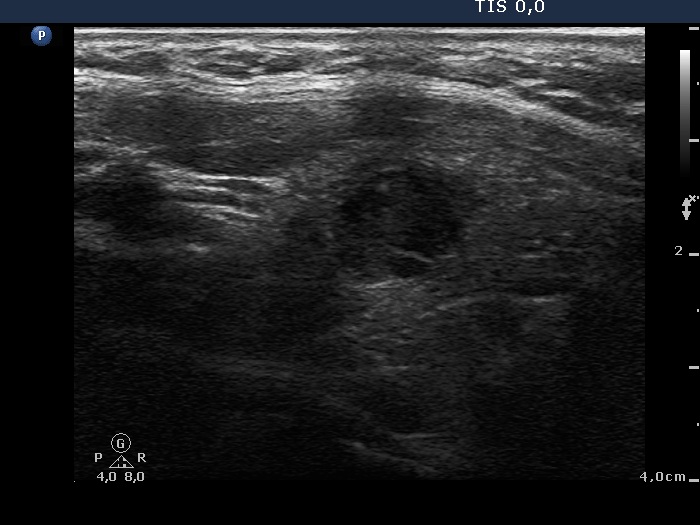

Second examination 7 years later (second row of images):

Clinical presentation. In the past 7 years, the patient had no complaints and therefore did not come to the proposed checkup either. Now he felt it was time to do an investigation.

Functional state: subclinical hypothyroidism with TSH 5.82 mIU/L, aTPO 98 U/mL.

Palpation: a hard nodule in the left lobe.

Ultrasonography. The presentation of the thyroid was essentially the same as 7 years ago. The only discrepancy was the lesion in the left lobe. Firstly, the size of the lesion have substantially increased to 25x18x25 mm (width, depth, and length, respectively), the volume was 5.89 mL which means that the volume became almost 8-times larger. Secondly, it was no more question whether the lesion was a pathological nodule or not. It turned out that this lesion is clearly a pathological nodule. Thirdly, in contrast to the former examination, the nodule has numerous microcalcifications and showed a clearly irregular, lobulated margins.

Aspiration cytology resulted in suspicion of papillary cancer.

Total thyroidectomy was performed, histopathology disclosed a T2 papillary cancer and Hashimoto's thyroiditis.

Comments:

We could not decide on the first ultrasound whether the lesion in the left lobe would be a nodule in a pathological sense. The presence of other similar areas decreased the possibility being the larger lesion a true nodule.

By reviewing the original smear, we found scattered numbers of grooves and two or three inclusions. It is difficult for a person to judge his or her own opinion, but it may well be that this pattern should not be judged as Bethesda III but as a suspicion of malignancy.